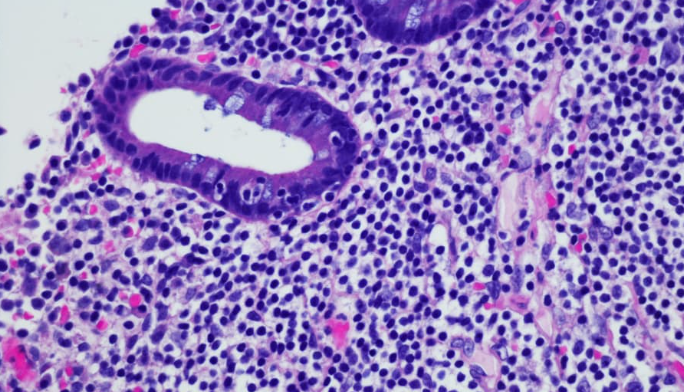

림프종 암은 면역체계의 중요한 부분인 림프계에서 발생하는 악성 종양입니다. 림프계는 림프절, 림프관, 비장, 골수 등으로 구성되어 있으며, 외부 세균이나 바이러스에 대응하는 방어 시스템입니다. 림프종은 크게 호지킨 림프종과 비호지킨 림프종으로 나뉘며, 세부적으로 수십 가지 종류가 있습니다.